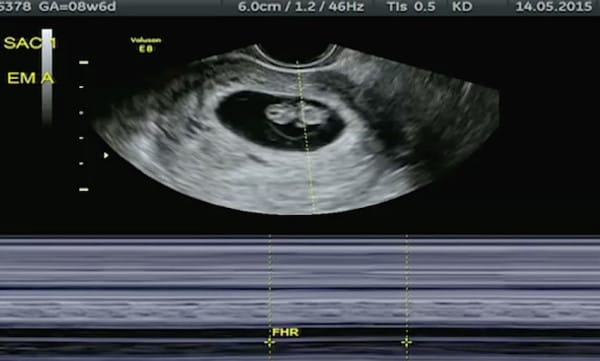

In gergo medico si chiama superfetazione ed è un fenomeno molto, molto raro. Si verifica quando, dopo la fecondazione di un ovulo e la formazione di un feto viene rilasciato un secondo ovulo che viene a sua volta fecondato.

Kate quindi è rimasta incinta della sua seconda bambina quando era già incinta di due gemellina, di cui una non è sopravvissuta.